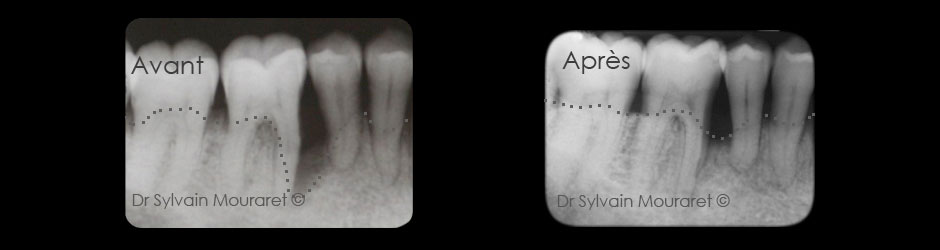

Régénération tissulaire